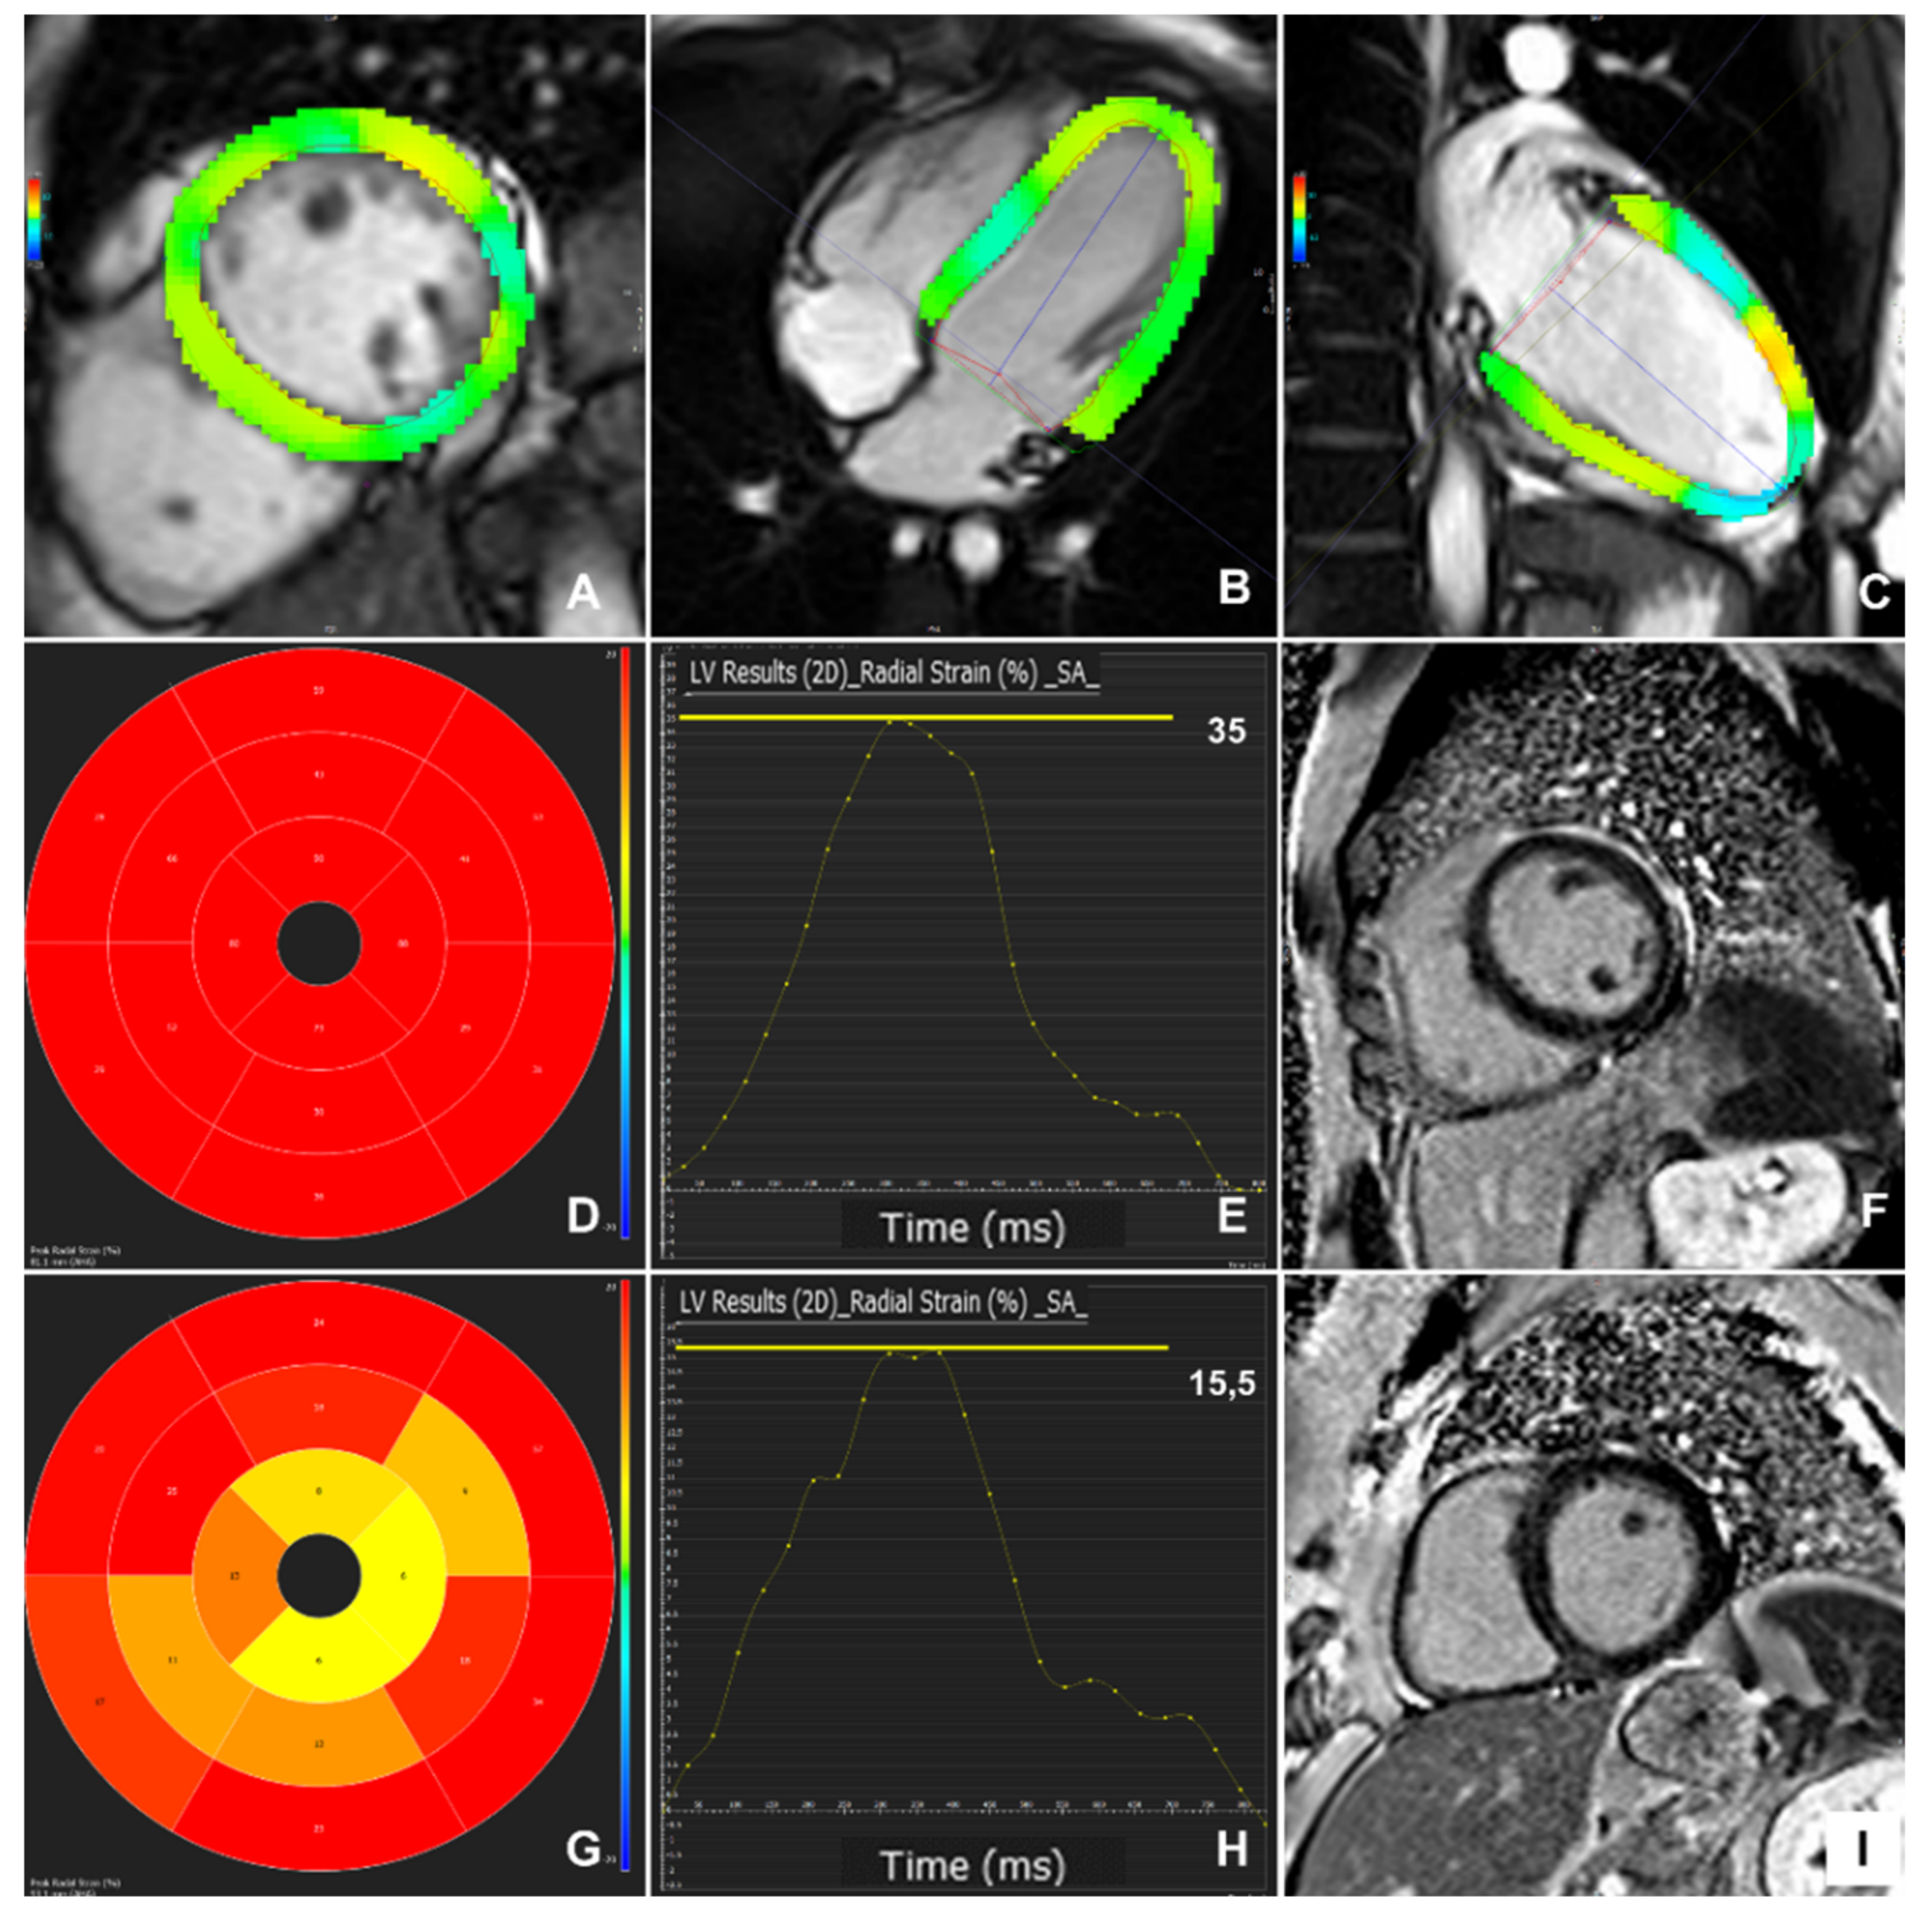

3.2. Myocardial Strain Findings

3.3. Myocardial Strain in Different Patient Groups